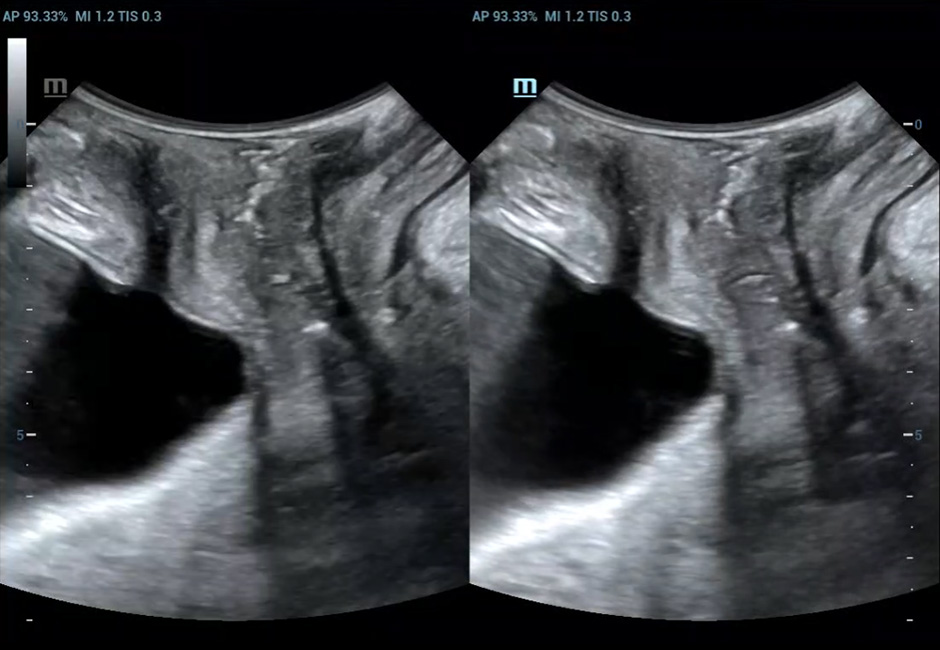

Cystocele-Uterine prolapse-Enterocele